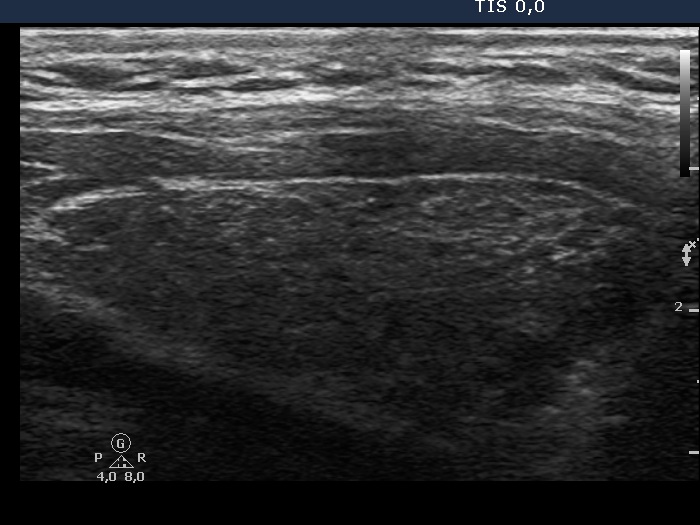

Case conp 085 (ultrasonographic picture 2)

Right lobe, longitudinal scan.